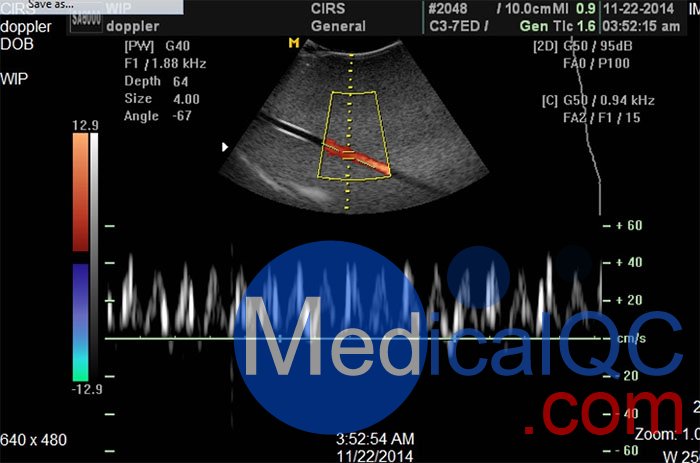

| CIRS 069多普勒超聲血流模擬器產(chǎn)品規(guī)格 | ||

| 血液模擬液 | ||

| 屬性 | 人類血液(37°C) | 血液模擬液(22°C) |

| 粘度(mPa) | 3 | 4±0.5 |

| 速度(m / s) | 1583 | 1570±30 |

| 衰減(dB / cm / MHz) | 0.15 | <0.1 |

| 后向散射(f 4 m -1 sr 1) | 4x10 -31 | 未測(cè)量 |

| 流體性質(zhì) | 非牛頓 | 牛頓 |